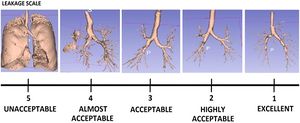

- 3.23 Optimizing Parameters of an Open-source Airway Segmentation Algorithm using Different CT Images